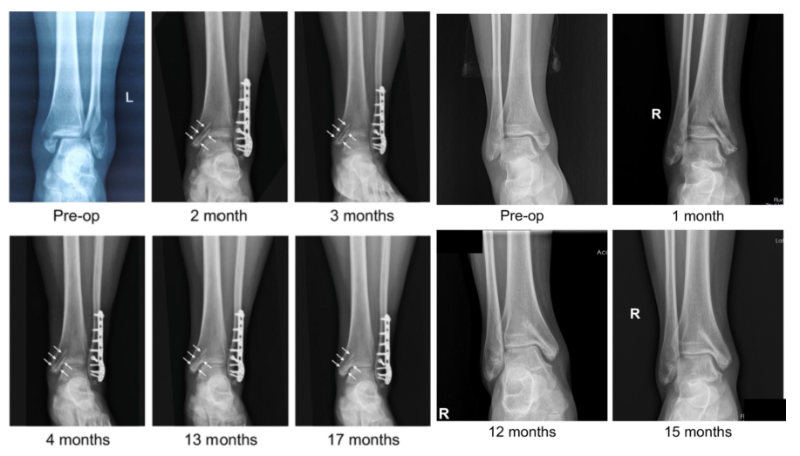

近日,國(guó)際骨科臨床轉(zhuǎn)化期刊《Journal of Orthopaedic Translation》在線發(fā)表了由上海交大戴尅戎院士、郝永強(qiáng)教授團(tuán)隊(duì)和丁文江院士、袁廣銀教授團(tuán)隊(duì)合作發(fā)表的可降解鎂合金骨釘1-2年的臨床試驗(yàn)觀察結(jié)果,所有患者術(shù)后內(nèi)踝骨折愈合,功能恢復(fù)。研究證實(shí)了可降解鎂合金螺釘治療內(nèi)踝骨折的臨床療效及其生物安全性,為全降解鎂合金植入物等高端醫(yī)療器械進(jìn)一步的臨床推廣應(yīng)用奠定了堅(jiān)實(shí)基礎(chǔ),相關(guān)成果以“Effectiveness and safety of biodegradable Mg-Nd-Zn-Zr alloy screws for the treatment of medial malleolar fractures”為題在線發(fā)表于Journal of Orthopaedic Translation,27 (2021) 96–100。這是國(guó)內(nèi)首個(gè)可降解醫(yī)用鎂合金臨床試驗(yàn)的公開(kāi)報(bào)道,也是國(guó)際首款含有功能涂層的可降解鎂合金骨釘?shù)呐R床試驗(yàn)結(jié)果的公開(kāi)報(bào)道,具有里程碑意義。

醫(yī)用鎂合金骨內(nèi)植物臨床試驗(yàn)研究突破性進(jìn)展(圖1)

醫(yī)用鎂合金骨內(nèi)植物臨床試驗(yàn)研究突破性進(jìn)展(圖2)